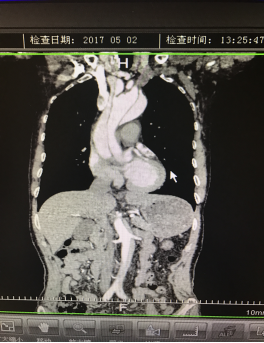

5月2號劉大伯照常早起干活,突然胸部劇烈疼痛,難以忍受,全身大汗,同時伴有右上肢發(fā)涼,他心想這次心絞痛比之前嚴(yán)重的多啊,趕緊叫上孩子到吉林國文醫(yī)院心血管內(nèi)科住院,患者長期高血壓病史,血壓一直控制不理想,大夫給他做了檢查,測左上肢血壓:82/45mmHg,右上肢血壓測不出,心率52次/分,右側(cè)肱動脈、尺動脈、橈動脈搏動消失,左側(cè)股動脈搏動較右側(cè)弱?!霸懔耍p側(cè)血壓差別這么大,是不是主動脈夾層了?”,接診大夫趕緊找來李主任,李主任反復(fù)詢問患者病情,表情突然凝重起來,患者胸痛這么明顯,血壓低的厲害,主動脈夾層的可能性很大。二話不說,李主任立即聯(lián)系影像科的醫(yī)生準(zhǔn)備做主動脈CTA,移動患者做檢查的過程大夫們非常小心,嚴(yán)密監(jiān)測患者血壓變化情況。兩個小時后結(jié)果出來了,主動脈夾層從升主動脈一直撕裂到左側(cè)髂總動脈?。?!